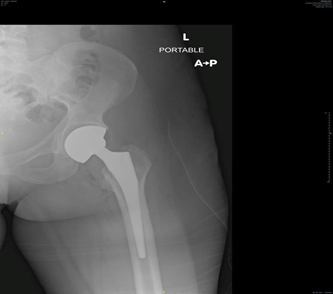

Total hip Replacement (THR) has become the treatment of choice in SCD patients with end-stage hip osteoarthritis resulting from symptomatic AVN. Patients are active young individuals at the time of surgery, that increase the risk of hip implant failure than those individuals having THA for primary osteoarthritis (OA).5 Rates of implant failure have been reported in early studies with arange from 30% to 60% in less than 5 years. This occurs often due to high functional demand of patients leading to failure of implant.9 More recent data showed improvement in survivorship of hip implant, but still overall complications are higher in sicklers relative to those individuals having THA for primary OA.10 Due to the skeletal abnormalities and medical conditions associated with SCD patients having THA, it is very important for the surgeon to understand the expected pre and postoperative course and also intraoperative considerations regarding these patients and how it can differ from patients having THA for primary OA (Figure 2).